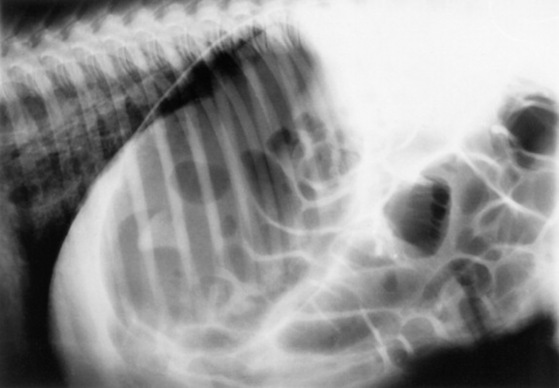

Serial thoracic radiographs are useful in monitoring the progress of a respiratory condition. Radiographic changes may either follow or precede changes in clinical condition, and major changes can occur surprisingly rapidly (Fig. 19-2). Clinical signs of pneumonia frequently resolve much earlier than chest radiographs and hemograms return to normal. Unfortunately, both ABG analysis and radiography are difficult to perform in field situations.

Fig. 19-2 A, Standing lateral chest radiograph of a 7-day-old thoroughbred filly with severe angular limb deformities that experienced an acute onset of severe respiratory distress and cyanosis after a walk outside the stall. Intubation and 100% oxygen administration raised the PaO2 to only 48 mm Hg. Severe pulmonary interstitial disease is present in the caudoventral lung fields, and the tentative diagnosis was bacterial pneumonia. No modifications were made in the treatment regimen (the same antibiotics being given for a wound were continued), and over the following 24 hours the filly clinically improved. B, Repeat radiographs taken 3 days after the first ones revealed marked resolution of the infiltrates. The diagnosis remains open, but pulmonary edema was suspected.